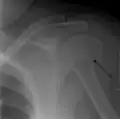

Proximal

Proximal humerus fractures most often occur among elderly people with osteoporosis who fall on an outstretched arm.[9] Less frequently, proximal fractures occur from motor vehicle accidents, gunshots, and violent muscle contractions from an electric shock or seizure.[10][5] Other risk factors for proximal fractures include having a low bone mineral density, having impaired vision and balance, and tobacco smoking.[11] A stress fracture of the proximal and shaft regions can occur after an excessive amount of throwing, such as pitching in baseball.[6]

Definitive diagnosis of humerus fractures is typically made through radiographic imaging. For proximal fractures, X-rays can be taken from a scapular anteroposterior (AP) view, which takes an image of the front of the shoulder region from an angle, a scapular Y view, which takes an image of the back of the shoulder region from an angle, and an axillar lateral view, which has the patient lie on his or her back, lift the bottom half of the arm up to the side, and have an image taken of the axilla region underneath the shoulder.[9] Fractures of the humerus shaft are usually correctly identified with radiographic images taken from the AP and lateral viewpoints.[12] Damage to the radial nerve from a shaft fracture can be identified by an inability to bend the hand backwards or by decreased sensation in the back of the hand.[5] Images of the distal region are often of poor quality due to the patient being unable to extend the elbow because of pain. If a severe distal fracture is suspected, then a computed tomography (CT) scan can provide greater detail of the fracture. Nondisplaced distal fractures may not be directly visible; they may only be visible due to fat being displaced because of internal bleeding in the elbow.[7]